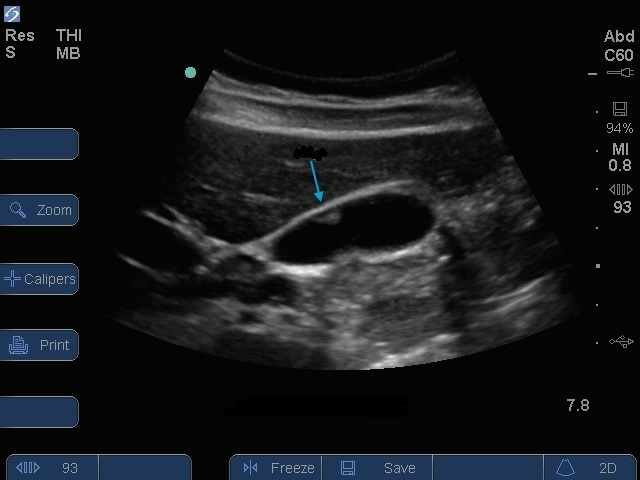

Imagen de pólipo en la vesícula biliar

Flecha azul: Pólipo